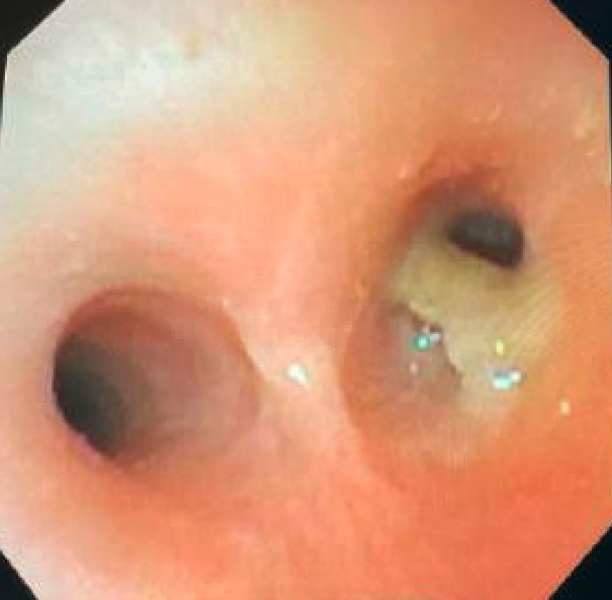

Airway Foreign Body